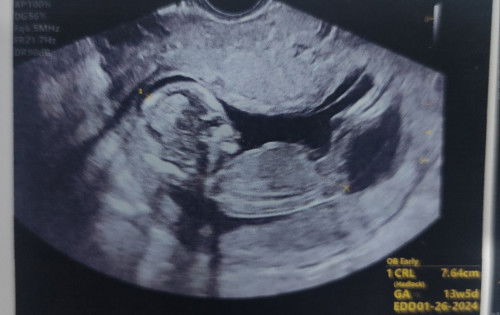

Shookt sa EDD ni Baby

All along i thought un dugo ko ng May 20-June 4 is menstruation, turns out upon having my TVS yesterday 13wks 5days na ako... nakakagulat! hindi ko akalain na possible pala un ganon... Akala ko 2mos pa lang ako kasi after June 4 hindi pa ulit ako niregla (un akala ko) so nag PT ako, and positive xa... Nakakatuwa na ang laki na pala ni baby ko... 🙂 *2nd Pic was taken May 29, na akala ko regla